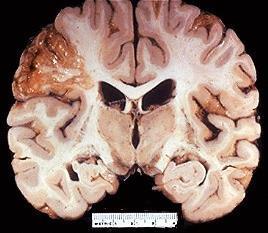

Arquiteturas de um fígado normal (à esquerda) e fibrótico.